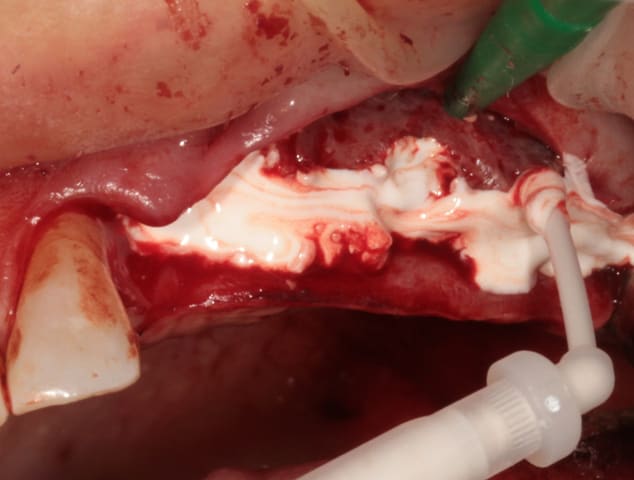

séchage compresse

Vitalos

préparation sutures

Merci de votre patience et rendez vous dans 6 mois pour la prothèse ou avant pour déposer si les Dieux ne sont pas avec la patiente et moi même.

PS à une semaine tout va bien